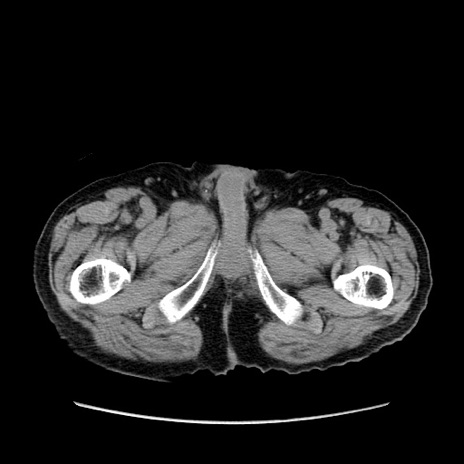

症例24(横断像)

【症例】80歳代男性

【主訴】左側腹部痛、嘔吐

【現病歴】本日早朝より左腹部に痛みあり。昼頃嘔吐認めたため、救急要請。

【既往歴】直腸癌(Mile手術)、胆摘

【身体所見】意識清明、BT 35.9℃、BP 221/93mmHg、SpO2 97%(RA) 、腹部:左ストーマ周囲に限局性の腹部膨隆あり。 膨隆部自発痛・圧痛あり・軟。

【データ】WBC 7700、CRP 0.09